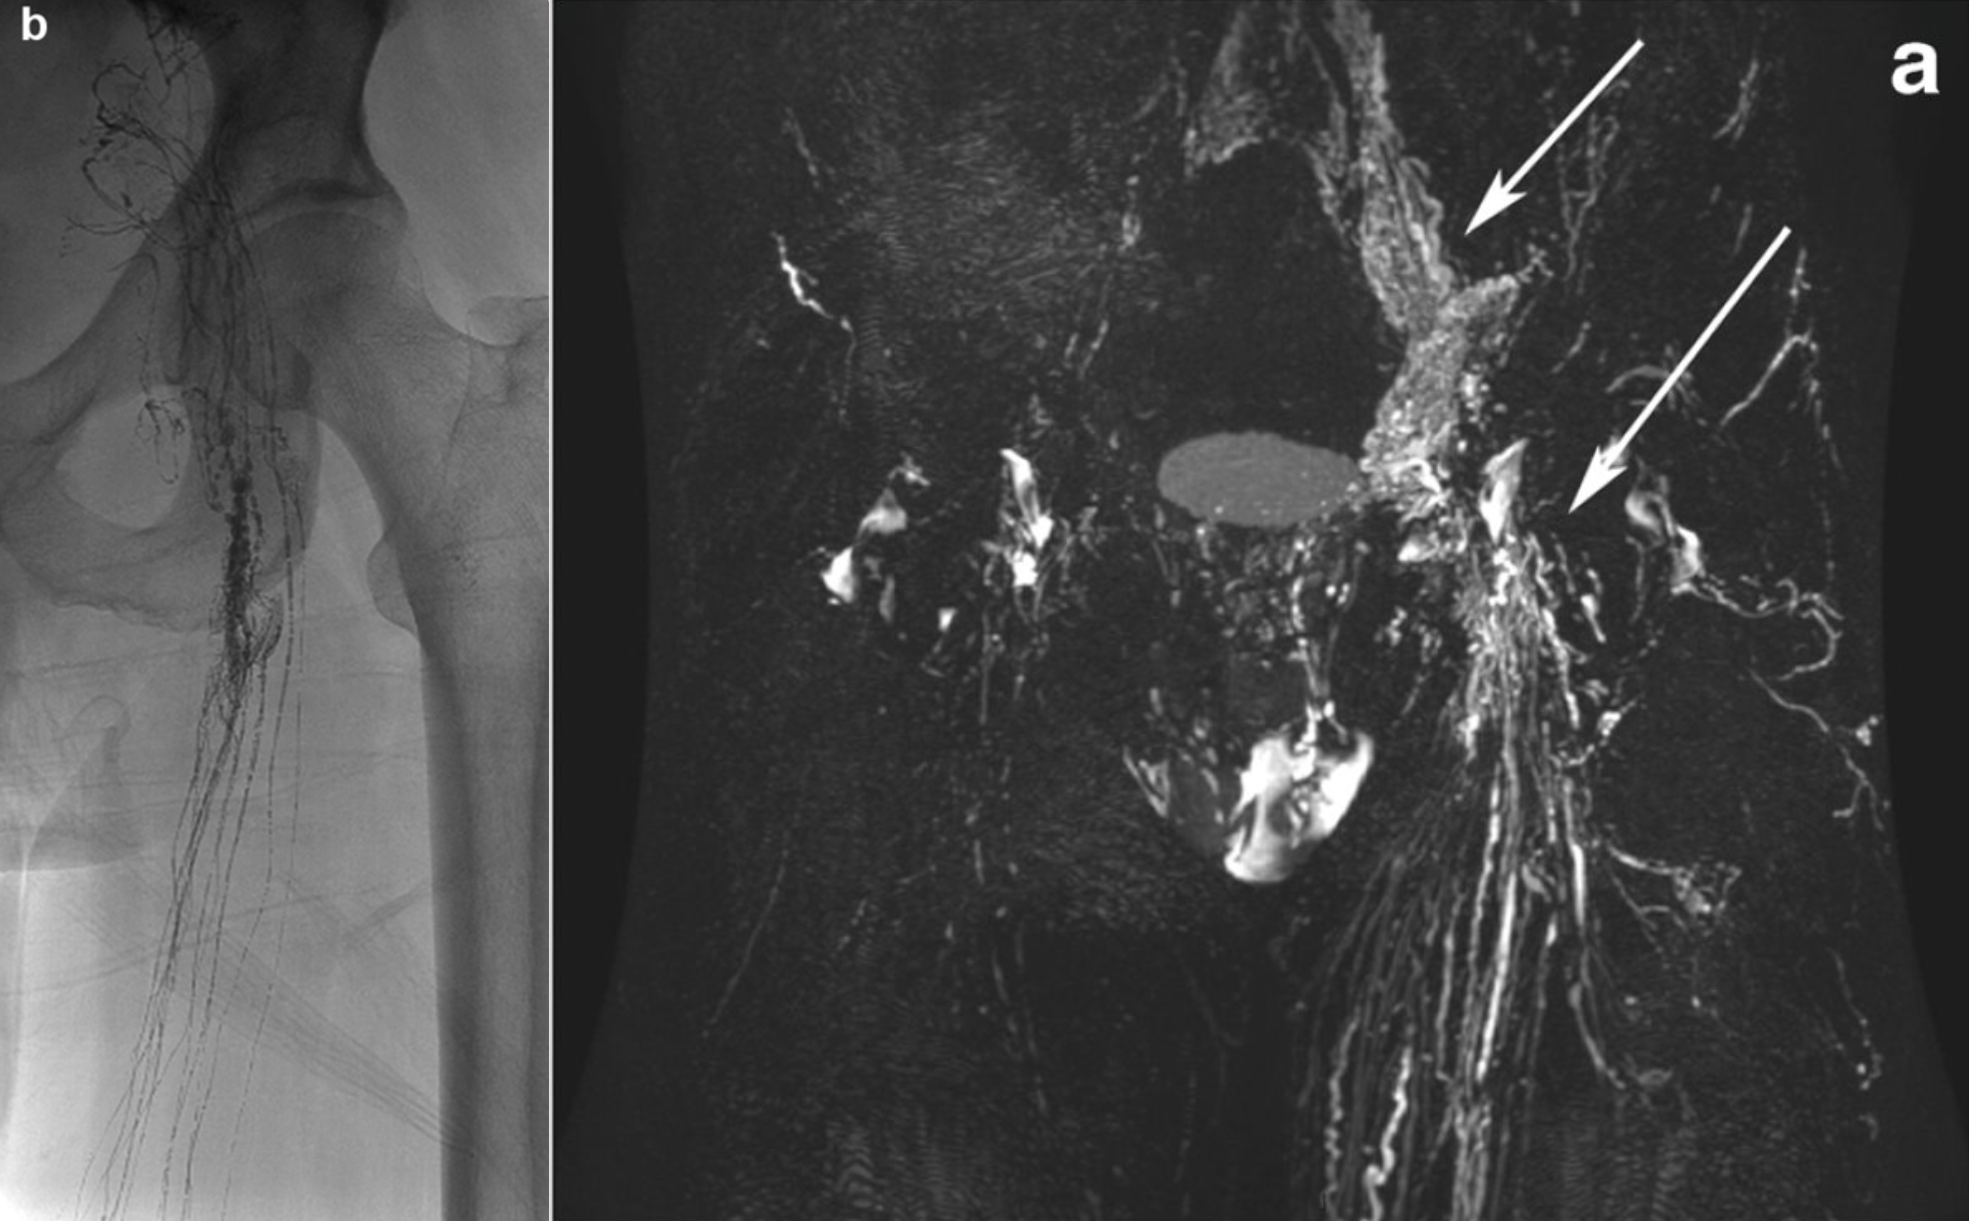

The lymphatic system transports tissue fluid, fats, and immune cells. Disorders can cause lymph leakage or drainage problems, leading to conditions such as chylothorax, lymphatic fistulas, or persistent fluid collections. Lymphangiography is a minimally invasive imaging technique in which contrast agent is injected into lymph vessels (usually in the foot or groin) to visualize the lymphatic system and detect leaks using MRI. It also enables treatment: leaking vessels can be sealed and abnormal connections corrected, often avoiding surgery. Our group uses lymphangiography for both precise diagnosis and minimally invasive therapy, allowing targeted treatment even of very small lymph vessels. Below you can see a the lymphatic system in the pelvis of a patient and the leakage causing lymph to exit (Fig. 6).